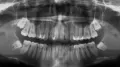

Здравствуйте. Была у стоматолога, она заметила внизу на челюсти две твердые шишки над пятерками, сказала, что возможно там зубы, так бывает. Они не беспокоят меня, раньше я их никогда не замечала. Цвет у них как у десны. Подскажите, что это? Заранее спасибо.

Добрый день. Обычно на нижней челюсти, в области пятых зубов, наблюдаются выпирающие костные образования в виде шариков. В этом нет ничего страшного, это строение челюсти. Что у вас я, к сожалению, не знаю (не вижу). Рекомендую обратиться на очный осмотр к врачу и сделать рентген-анализ для выявления причины.